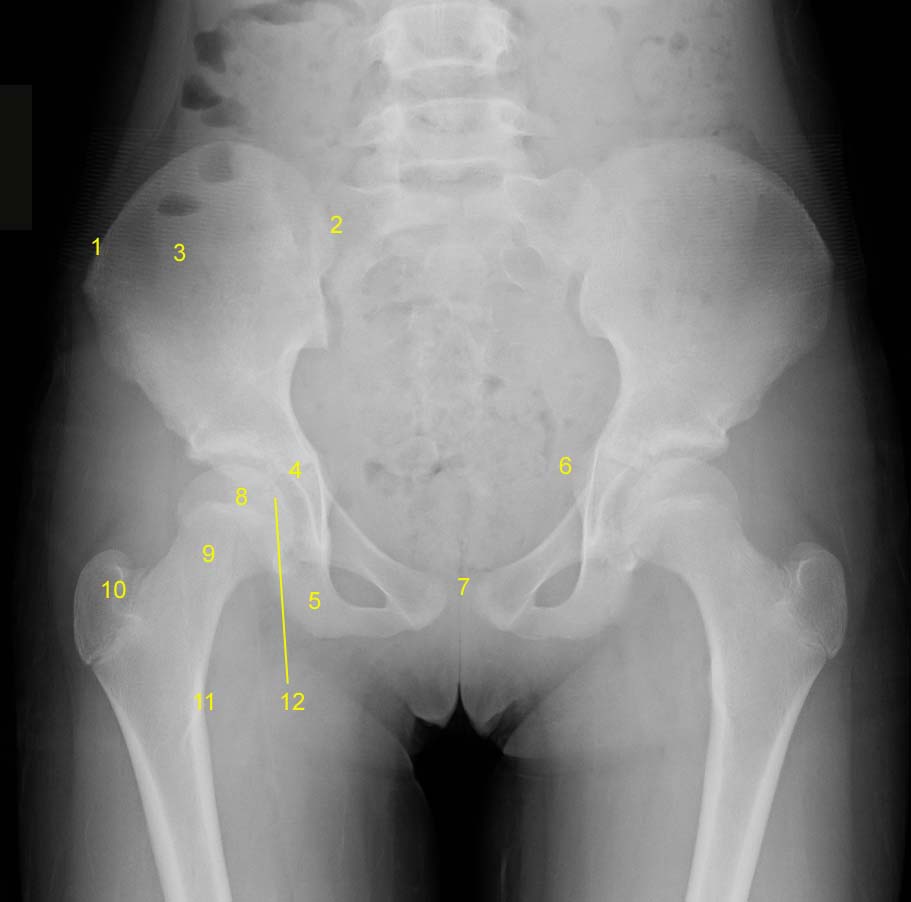

Pelvis x-ray (AP)

Labeled Study

Legend